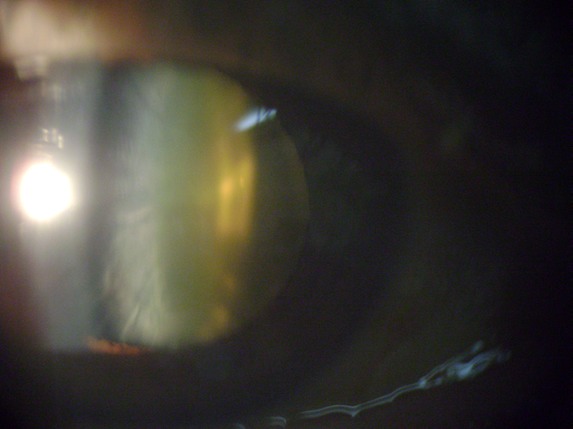

IMG 1156

Catarata Nuclear y Cortical Anterior